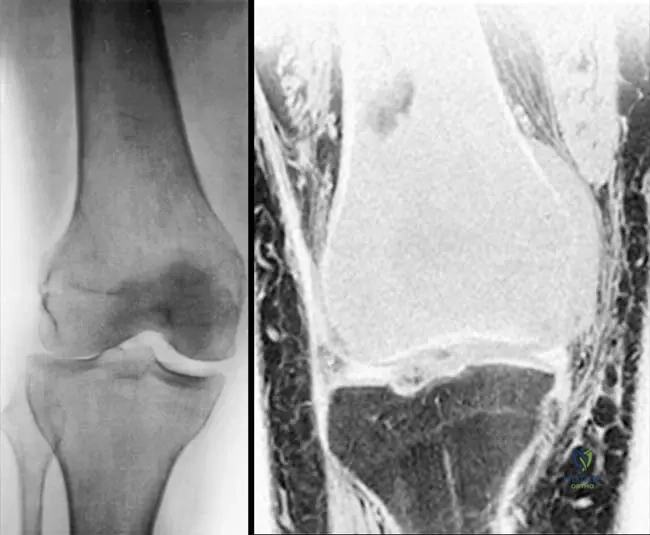

Rationale: The clinical context for Fig. 8.22 a, b explicitly links "Short stature and osseous deformity secondary to Ollier’s disease" with multiple enchondromas. Ollier's disease is characterized by multiple enchondromas, often unilateral, leading to significant skeletal deformities and growth disturbances. The other conditions are distinct skeletal dysplasias or disorders not primarily characterized by multiple enchondromas.

Rationale: The clinical context for Fig. 8.22 a, b explicitly states "Short stature and osseous deformity secondary to Ollier’s disease." Ollier's disease is characterized by multiple enchondromas, often unilateral, leading to significant skeletal deformities and growth disturbances. Solitary enchondroma does not involve multiple lesions. Maffucci syndrome includes hemangiomas, not mentioned. Chondrosarcoma is malignant. Fibrous dysplasia is a different bone disorder.